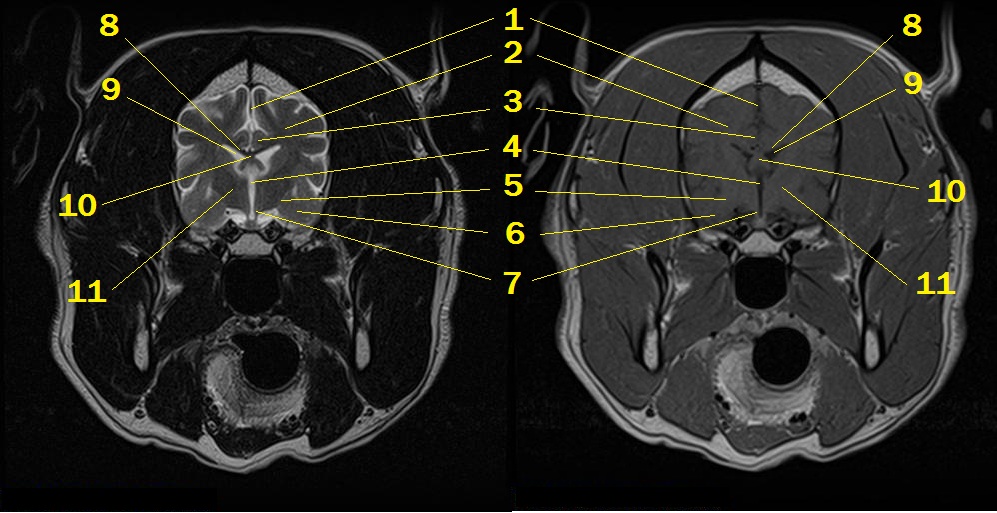

MRI anatomy 6

Q. Identify the structures labeled below:

1. falx cerebri

2. centrum semiovale

3. cingulum in cingulated gyrus

4. 3rd ventricle

5. optic tract

6. amygdaloid body in the piriform lobe

7. hypothalamus

8. corpus callosum

9. lateral ventricle

10. body of the fornix

11. thalamus